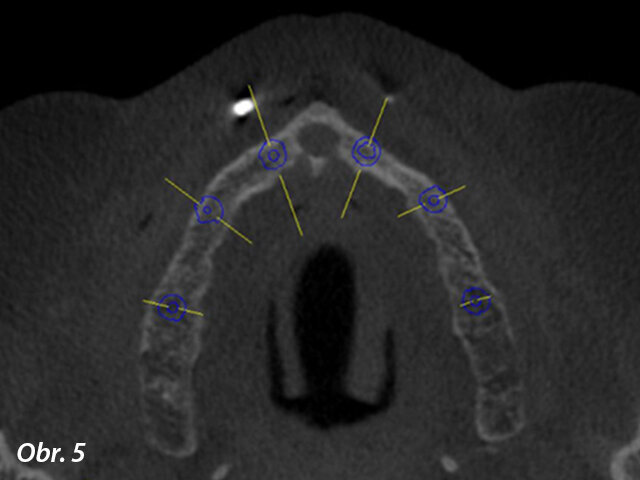

Prostřednictvím softwaru coDiagnostiX jsme zjistili, že je k dispozici dostatek kosti pro zavedení implantátů, kromě dvou oblastí, do nichž bude nutno transplantovat kostní štěp (obr. 5, 6). Bylo naplánováno celkem šest implantátů s adekvátním rozložením po oblouku, které vytvoří podpěru pro žvýkací síly a zabrání jednostranné zátěži (obr. 7). Zavedení implantátů bylo naplánováno za použití chirurgické šablony (obr. 8) a na implantáty měla být hned po chirurgickém zákroku našroubována provizorní náhrada – jednalo se tedy o protokol okamžitého zatížení.